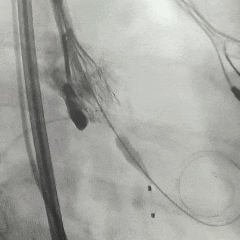

手术过程

根部造影:可见瓣叶钙化,几乎无反流

20mm球囊扩张,无腰,球囊轻微滑动

瓣膜系统定位

瓣膜展开后造影评估,深度可,无明显瓣周漏

多角度造影评估:瓣膜深度形态合适,冠脉灌注良好

脱钩后造影:瓣膜无位移,同轴性良好,无瓣周漏

术后超声测量

即刻瓣口流速2.2m/s;平均压差9mmHg,手术结束